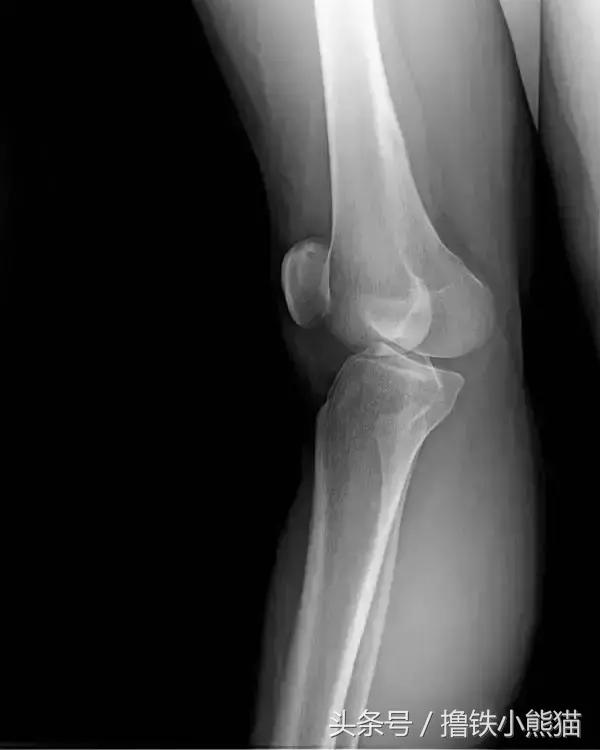

下面是一张膝关节超伸的X 光片,从光片中能看出关节前侧和髌骨与股骨(大腿骨)之间的缝隙都很小。

而正常的状态应该是两个骨头在关节面均匀接触的,整个支撑面上的重力应该是平均分布的,超伸时则加重了关节前侧的压力,从而诱发膝关节疼痛。